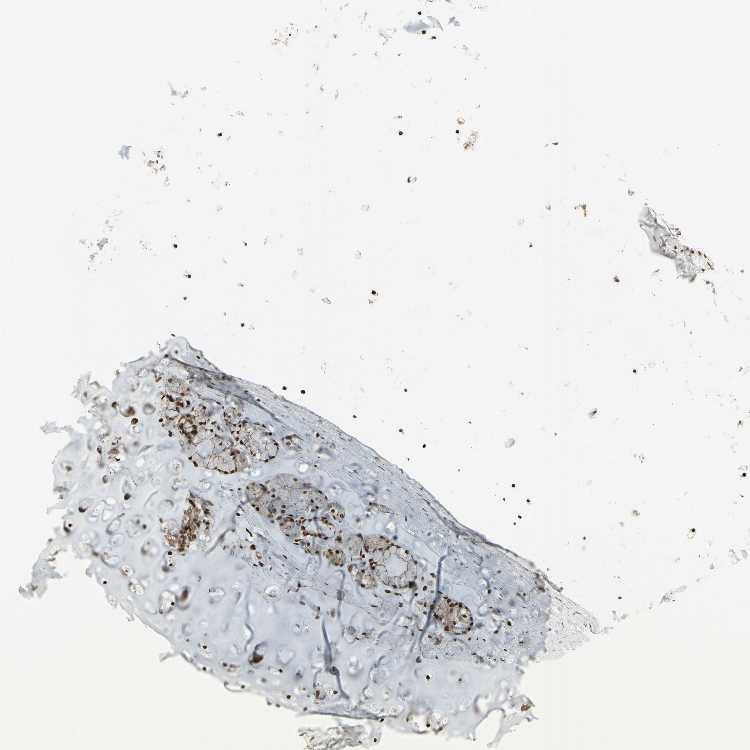

ADIPOSE TISSUE - Antibody stainingi

Antibody staining in the annotated cell types in the current human tissue is reported as not detected, low, medium, or high, based on conventional immunohistochemistry profiling in selected tissues. This score is based on the combination of the staining intensity and fraction of stained cells.

Each image is clickable and will lead to virtual microscopy that enables deeper exploration of all samples and also displays staining intensity scores, fraction scores and subcellular localization as well as patient and tissue information for each sample.

Antibody CAB012265

Adipocytes Medium